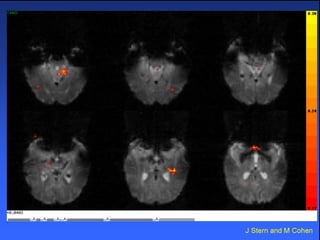

Interictal Spikes, fMRI

Hippocampal T2 signal changes

Hippocampal T2 signalchanges after prolonged febrile seizures